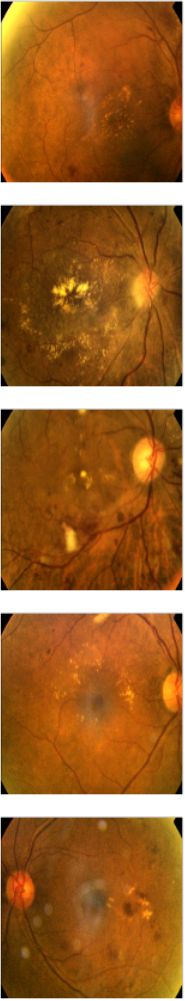

Finally, we randomly select some input images (see Figure 4) for demonstrative purposes. We pass the selected images through the InceptionV3 model (since it had the highest accuracy) to generate localisation maps and overlay the generated maps on the input images, as shown in Figure 4. We observe that the model generates a blurry image in Figure 4. The blurry effect can be attributed to the typical loss of spatial resolution as images pass through deep convolutional models. The blurry image in this case is the result of Grad-CAM. It may not be as useful until we map it on the input images. We see in Figure 4 that the Grad-CAM has highlighted regions of interest on the input images after mapping.

(a) Input

(b) Grad-CAM

(c) Overlaid Grad-CAM